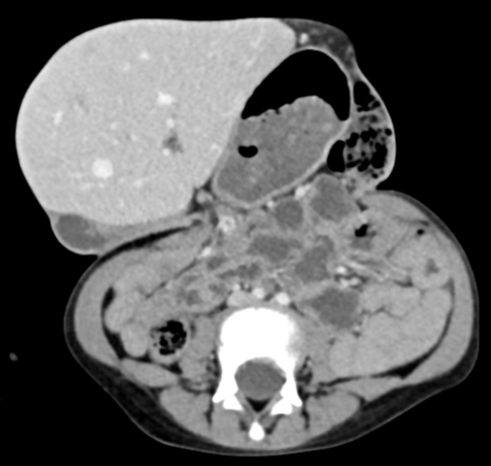

CT Scanner

DD Gastroschisis

omphalocèle omphalocele